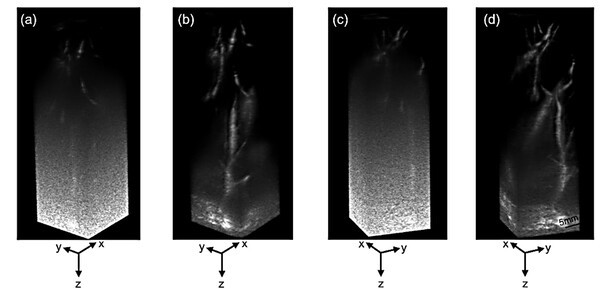

이에 연구팀은 여러 각도에서 영상을 합성하는 평면파 기법을 정밀하게 최적화하고, 신호를 암호화해 세기를 높이는 ‘코드화 여기(Coded Excitation)’ 기술을 결합해 이러한 한계를 극복했다. 이를 통해 조영제 없이도 피부 아래 약 7cm 깊이의 혈관을 고해상도로 영상화하는 데 성공했다.

연구팀은 건강한 성인의 간과 비장을 대상으로 생체 내 실험을 진행해 초당 27프레임의 속도로 혈류의 움직임을 실시간 포착했고, 기존 대비 대조도-잡음비(CNR)가 약 9~10dB 향상되는 성과를 얻었다. 또한 미국 FDA 및 IEC 기준에 따른 안전성 검증에서도 장시간 촬영 시 프로브 과열 없이 안정적인 에너지 수준을 유지함을 확인했다.